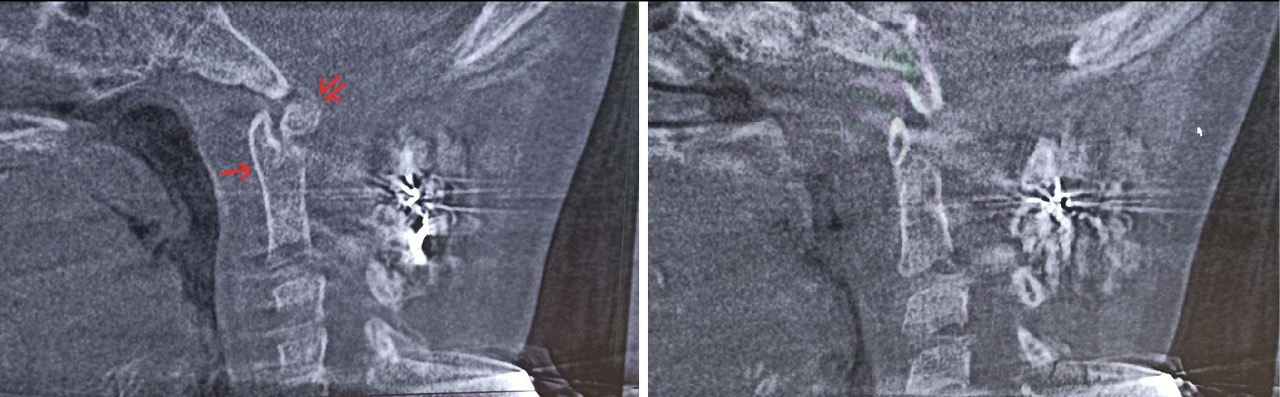

Для оценки ситуации в динамике была проведена КЛКТ, на которой на фоне динамической нерезкости (ребенок был неусидчив) и артефактов от металлоконструкции было отмечено следующее: суставные рентгеновские щели в латеральных атлантоаксиальных суставах: справа – не прослеживается, слева – неравномерно сужена до 0,4 мм в наиболее узком месте (рис. 6). Рентгеновская щель срединного атлантоаксиального сустава в сагиттальной плоскости не прослеживается (рис. 7А), в парасагиттальной плоскости – прослеживается, неравномерная (рис. 7Б). Зубовидный отросток С2 позвонка визуализируется в виде 2 фрагментов, дистальный из которых вместе с передней дужкой С1 позвонка представлен в виде не полностью слитного костного образования. Проксимальный фрагмент, лоцирующийся в проекции верхушки зубовидного отростка С2 позвонка, представлен в виде свободно лежащего отломка с неравномерно склерозированным контуром в проекции диастаза (см. рис. 7). Данная рентгенологическая картина соответствует состоянию после оперативного лечения по поводу травмы шейного отдела позвоночника со стабилизацией металлоостеосинтезом С1–С2 позвонков. Неправильно сросшийся перелом зубовидного отростка С2 позвонка. Частичный анкилоз срединного атлантоаксиального сустава и полный анкилоз правого латерального атлантоаксиального сустава.

Рис. 7. Конусно-лучевая компьютерная томография краниовертебральной области, сагиттальный срез (А), парасагиттальный срез (Б). Стрелкой отмечено место анкилоза срединного атлантоаксиального сустава. Двойной стрелкой обозначен свободно лежащий апикальный костный фрагмент зубовидного отростка аксиса